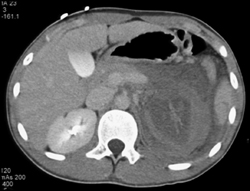

Traumatic Aortic Dissection in Arch